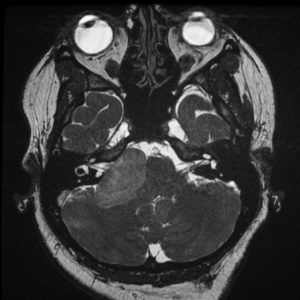

U dây VIII

Lượt xem: 140» 24-11-2018 -

U dây VIII

Lượt xem: 131» 24-11-2018 -

U dây VIII

Lượt xem: 143» 24-11-2018 -

U dây VIII

Lượt xem: 155» 24-11-2018 -